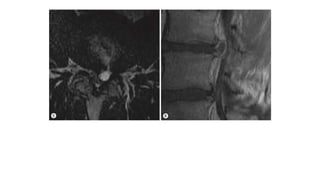

Juxtafacet (Ganglion) Cyst. Sagittal (A) and axial (B) T2

weighted images. The T2 weighted image shows a small cystic

lesion arising from the anterolateral aspect of the right facet

joint L5 to S1 compressing the L5 nerve at the level of the

neuroforamen.

A synovial cyst at L4–L5.Bilateral degenerated facet joint effusions with a left-sided synovial

cyst compressing the left dorsal aspect of the thecal sac